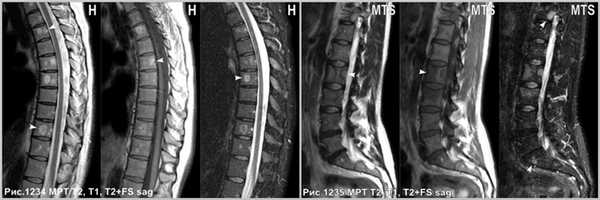

Множественные гемангиомы, поражающие ряд позвонков (головки стрелок на рис.1234). Метастазы, поражающие тела позвонков (головки стрелок на рис.1235).

Иногда встречаются множественные гемангиомы, поражающие ряд позвонков, что может осложнить дифференциальную диагностику со вторичным, метастатическим поражением тел позвонков. Однако, гемангиомы имеют продольную исчерченность, что не встречается у метастазов. Гемангиомы возникают вблизи базивертебральной вены и, часто связаны с ней, и венами позвонка, так же гемангиомы часто имеют жировой сигнал, а метастазы расположены в телах позвонков хаотично и всегда, даже в случае склеротических очагов сопровождаются отёком костного мозга, свидетельствующем о реактивной костной реструктуризации и деструкции. Гемангиомы крайне редко распространяются за пределы тела пораженного позвонка, а метастазы весьма часто приводят к деформации тела позвонка, распространяются за его пределы. Кроме того, метастазы редко поражают исключительно позвоночник, сопровождаясь лимфоаденопатией узлов средостения, парааортальных, паракавальных групп, а так же возможна визуализация очагов в печени и лёгких, при анализе захваченных на сканировании областей.